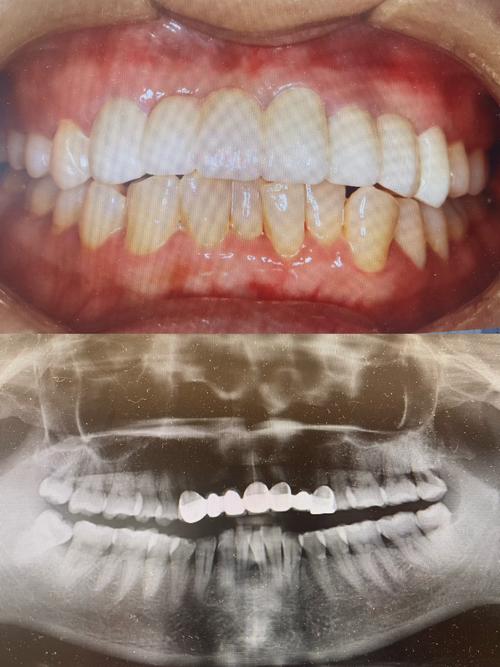

- 术前检查与方案设计:拍摄口腔全景片、CBCT,检查牙周健康、牙髓活力;结合面部比例(微笑线、中线对称)、肤色设计牙冠形态和颜色,确定是否需要邻牙预备(如牙缝过大时调整邻牙形态)。